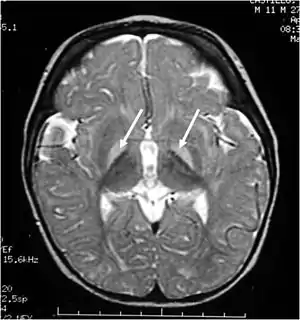

| Brain MRI. Hyperintense basal ganglia lesions on T2-weighted images. | |

These impairments are associated with lesions in the basal ganglia, auditory nuclei of the brain stem, and oculomotor nuclei of the brain stem. Cortex and white matter are subtly involved. Cerebellum may be involved. Severe cortical involvement is uncommon.